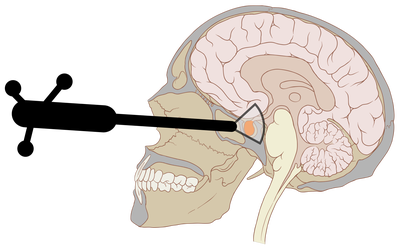

We are working to develop new technologies that combine a new type of camera system, referred to as hyperspectral, with Artificial Intelligence (AI) systems to reveal to neurosurgeons information that is otherwise not visible to the naked eye during surgery. Two studies are currently bringing this “hyperspectral” technology to operating theatres. The NeuroHSI study uses a hyperspectral camera attached to an external scope to show surgeons critical information on tissue blood flow and distinguishes vulnerable structures which need to be protected. The NeuroPPEye study is developing this technology adapted for surgical microscopes, to guide tumour surgery.

Christian Baker will be presenting on “Real-Time Ultrasonic Tracking of an Intraoperative Needle Tip with Integrated Fibre-optic Hydrophone” as part of the Tissue Characterization & Real Time Imaging (AM) poster session.